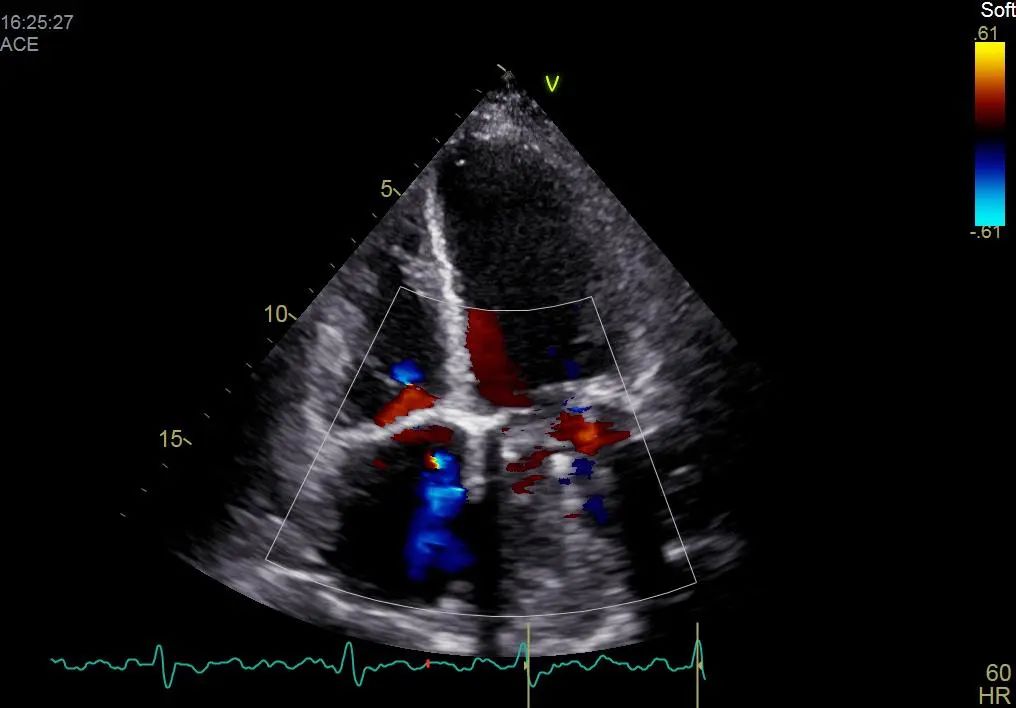

术后彩超影像